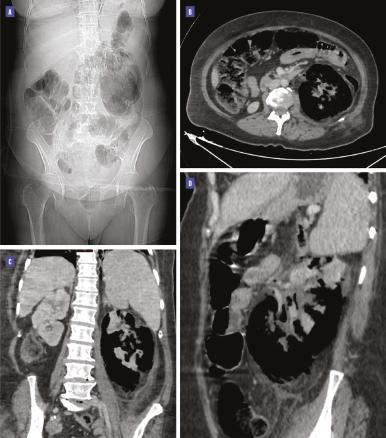

Une échographie rénovésicale est réalisée dans un premier temps, objectivant de larges zones hyperéchogènes avec atténuation postérieure masquant l’ensemble du rein gauche et posant l’indication d’un complément d’exploration scanographique.

La tomodensitométrie (TDM) abdominopelvienne avec injection de produit de contraste montre la présence de gaz dans le parenchyme rénal gauche et la voie excrétrice supérieure avec une destruction parenchymateuse diffuse, et une extension des bulles au-delà du fascia de Gerota, sans obstacle visible, en rapport avec une pyélonéphrite emphysémateuse de stade 3B selon la classification de Huang et Tseng (figure).